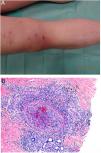

HistopathologyCell morphology varies in IVLBCL. Centroblasts, immunoblasts, and plasmablasts are observed. Their intravascular growth pattern may be dyscohesive (isolated intraluminal cells), cohesive (cells occluding the lumen), or marginal (cells adhering to the endothelium). The atypical cells are CD20+ and for the most part do not derive from germinal center B cells (CD10−, BCL6+/−); they express MUM-1 proteins (Fig. 8). Coexpression of CD5 has been reported in nearly 40% of cases, and the Ki-67 proliferation index is usually elevated (around 90%).44,45 The role of nonlesional skin biopsy for the diagnosis of IVLBCL is an important issue currently under debate. Even though there is no consensus on its utility in the literature, biopsies that sample adipose tissue have been reported to offer good sensitivity (near 80%) and specificity near 100%.46 Atypical CD30+ T-cell proliferation found in tissue samples requires particular attention in the differential diagnosis of IVLBCL. This type of pseudolymphoma has been described in relation to inflammatory diseases, tumors, and trauma.47,48

Intravascular large B-cell lymphoma. A, Capillary partially occluded by large blastic-appearing cells. Hematoxylin-eosin, magnification × 400. B–C, Immunohistochemical positivity for CD20 and MUM-1, respectively. Magnification × 400. D, Elevated Ki-67 antigen proliferation. Magnification × 400.